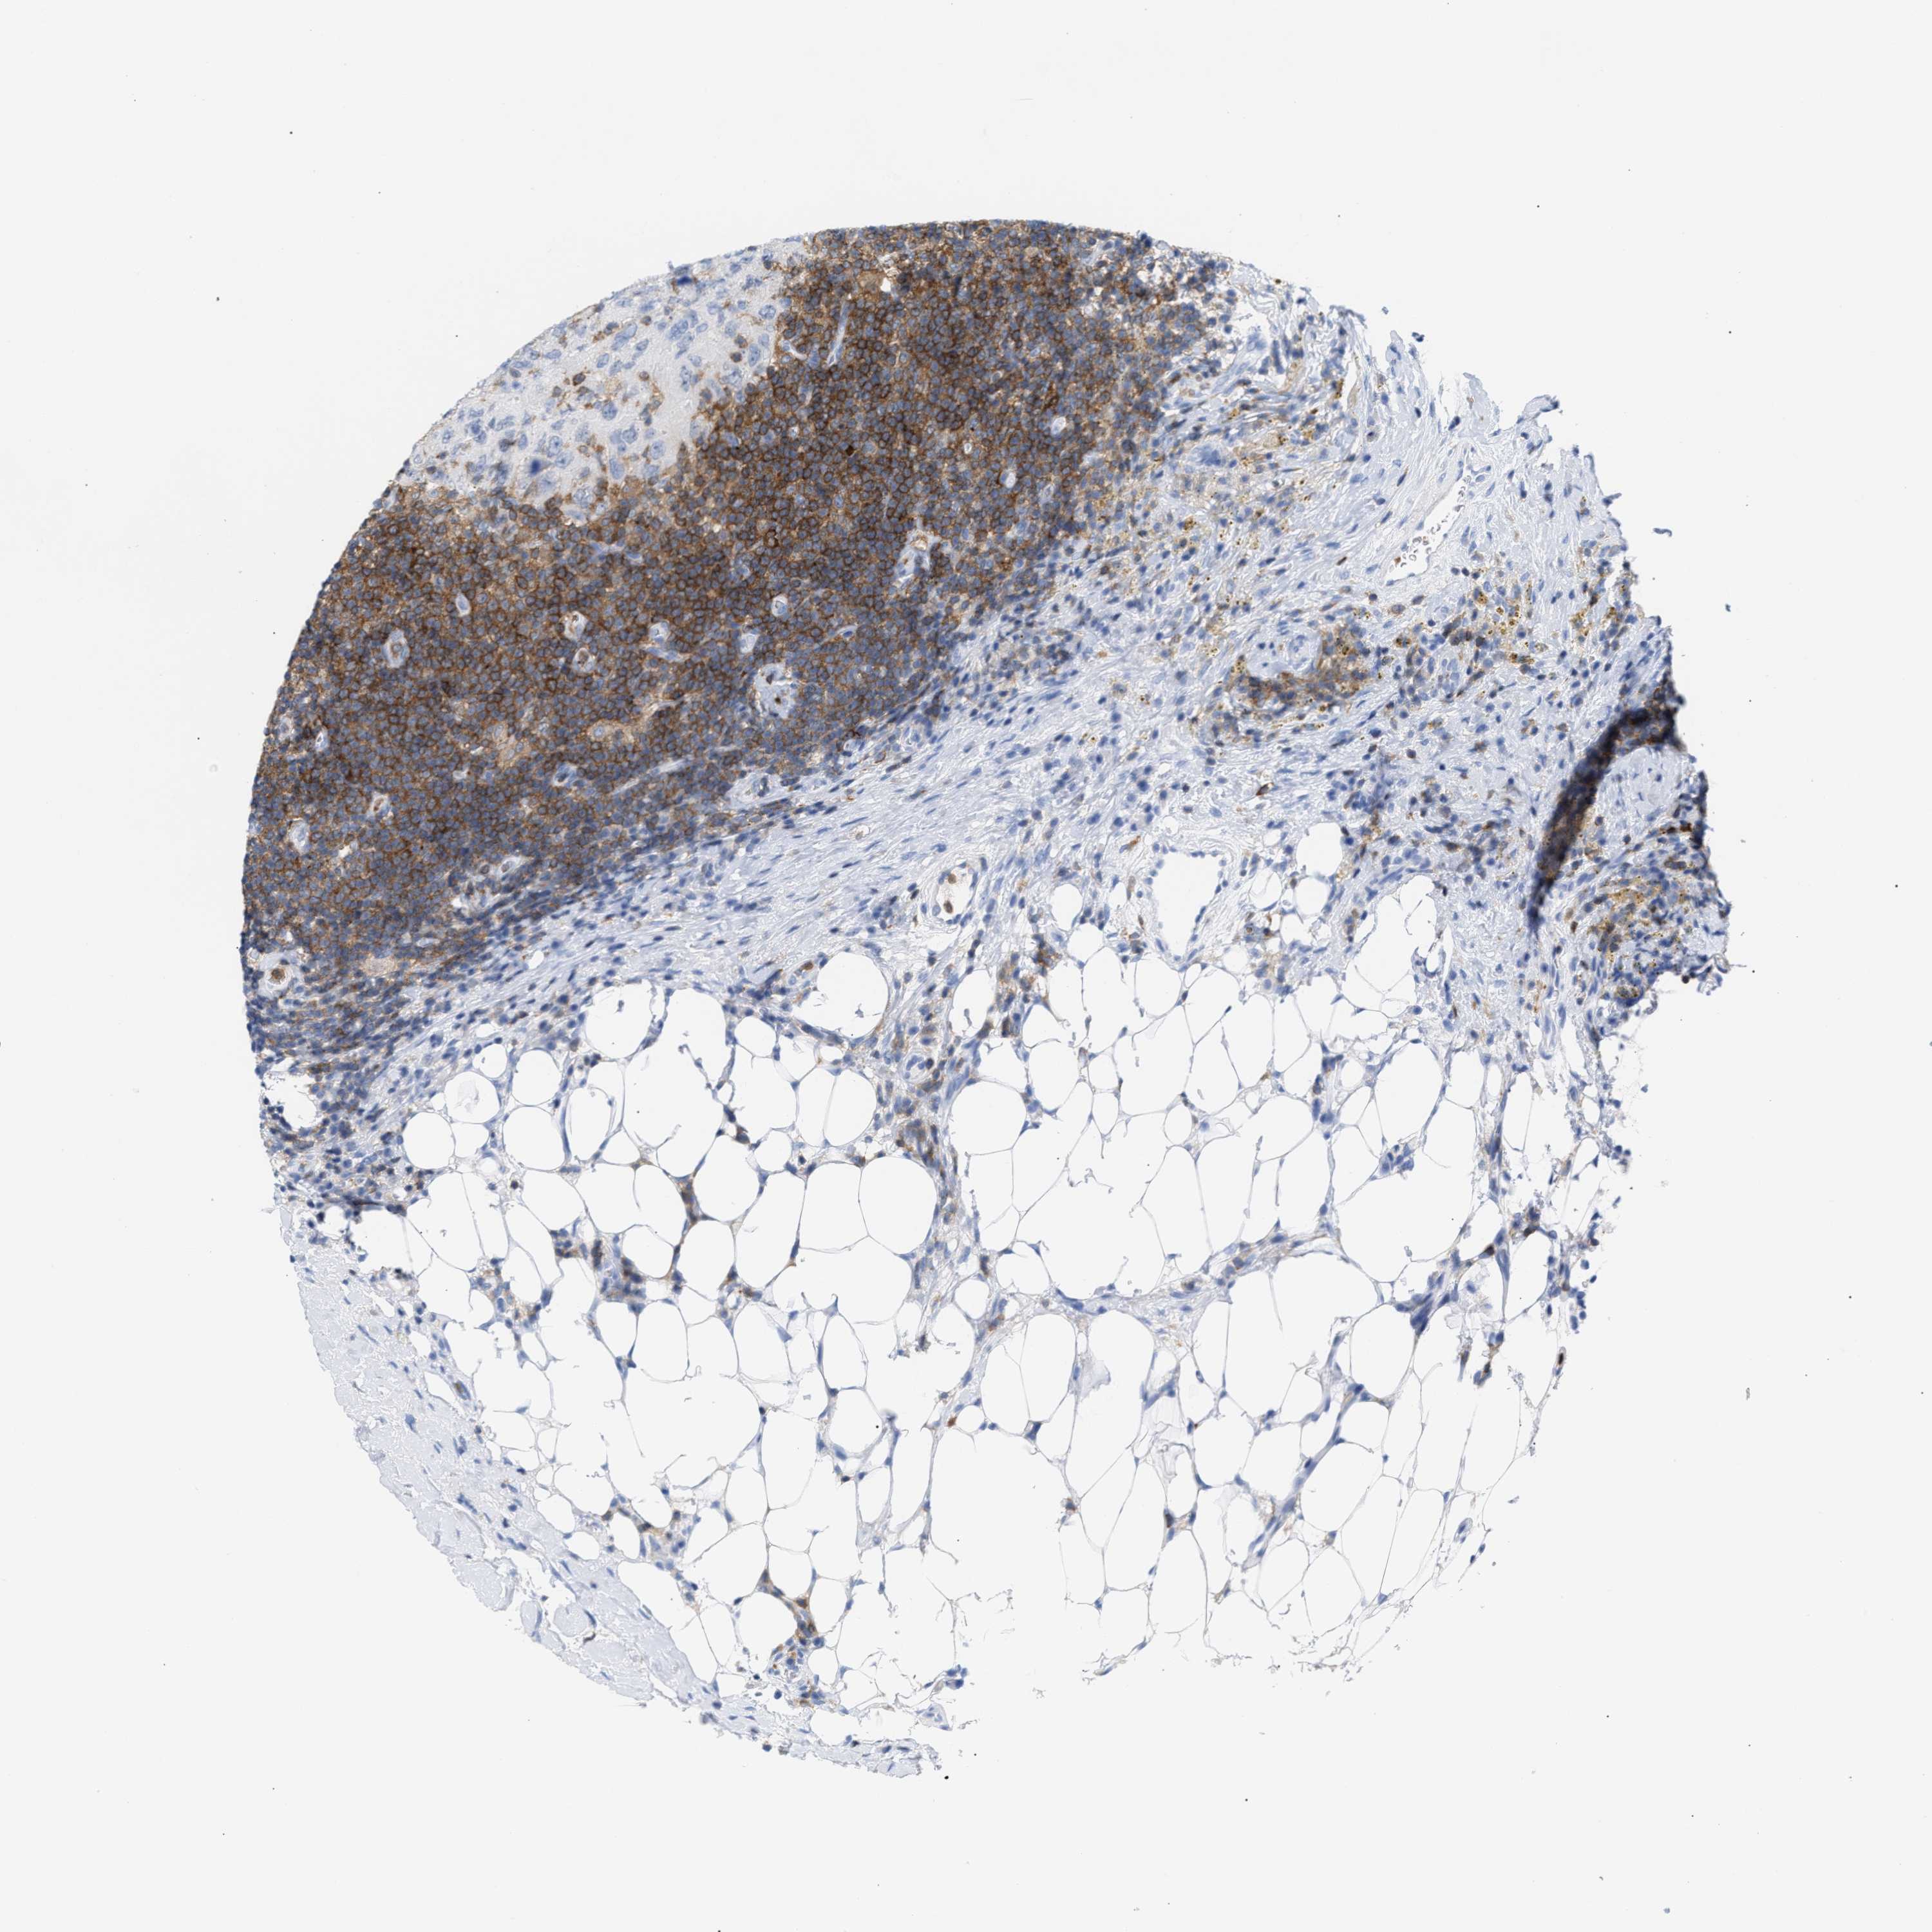

CANCER BREAST CANCER Show tissue menu

BRCA TCGA BRCA VALIDATION PROTEIN EXPRESSION

ANTIBODIES

AND

VALIDATION